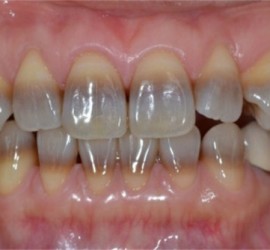

Аномалии строения и пороки развития зубов Пороки тканей зуба многообразны, они могут проявляться изолированно и сочетаться с аномалиями строения и пороками развития органов и систем всего детского организма, в том числе челюстно-лицевой области. Ткани зуба имеют эктодермальное (эмаль) и мезодермальное (дентин, пульпа, цемент) происхождение. В связи с этим пороки эмали […]